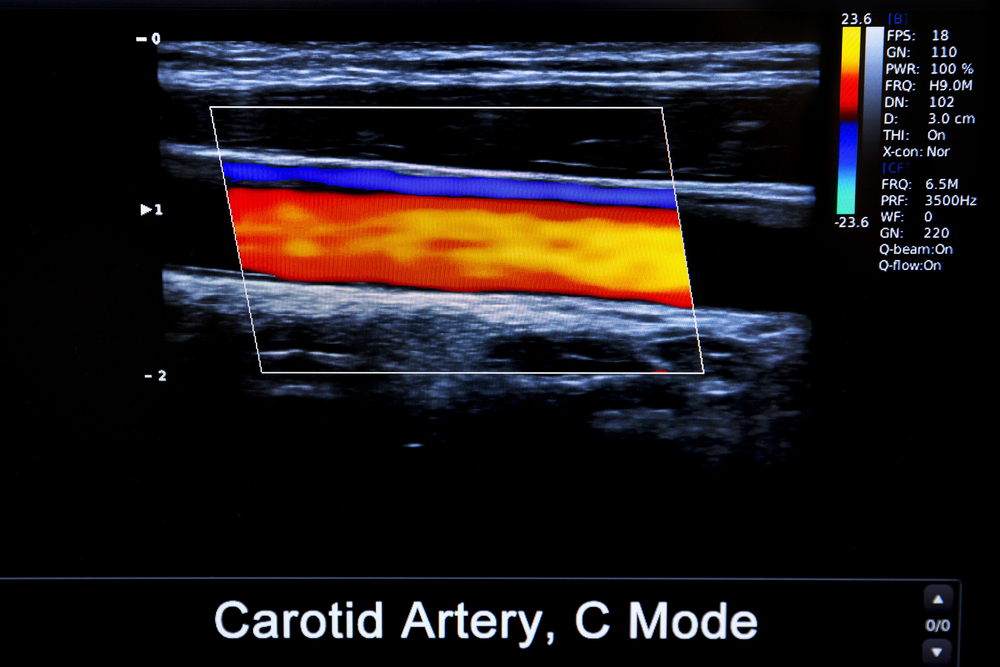

A Carotid Ultrasound provides detailed, real-time images of your carotid arteries, which are the primary blood vessels delivering oxygen-rich blood to your brain. These images are carefully analyzed by a radiologist—a physician who specializes in reading imaging tests. Once the review is complete, the radiologist prepares a detailed report and sends it to your primary healthcare provider.

Unlike MRIs or CT scans, Carotid Ultrasound offers immediate, real-time imaging of blood flow to the brain, helping doctors detect problems early.

It provides high-resolution visuals of your carotid arteries and soft tissues, helping doctors see even minor narrowing or early signs of plaque buildup.